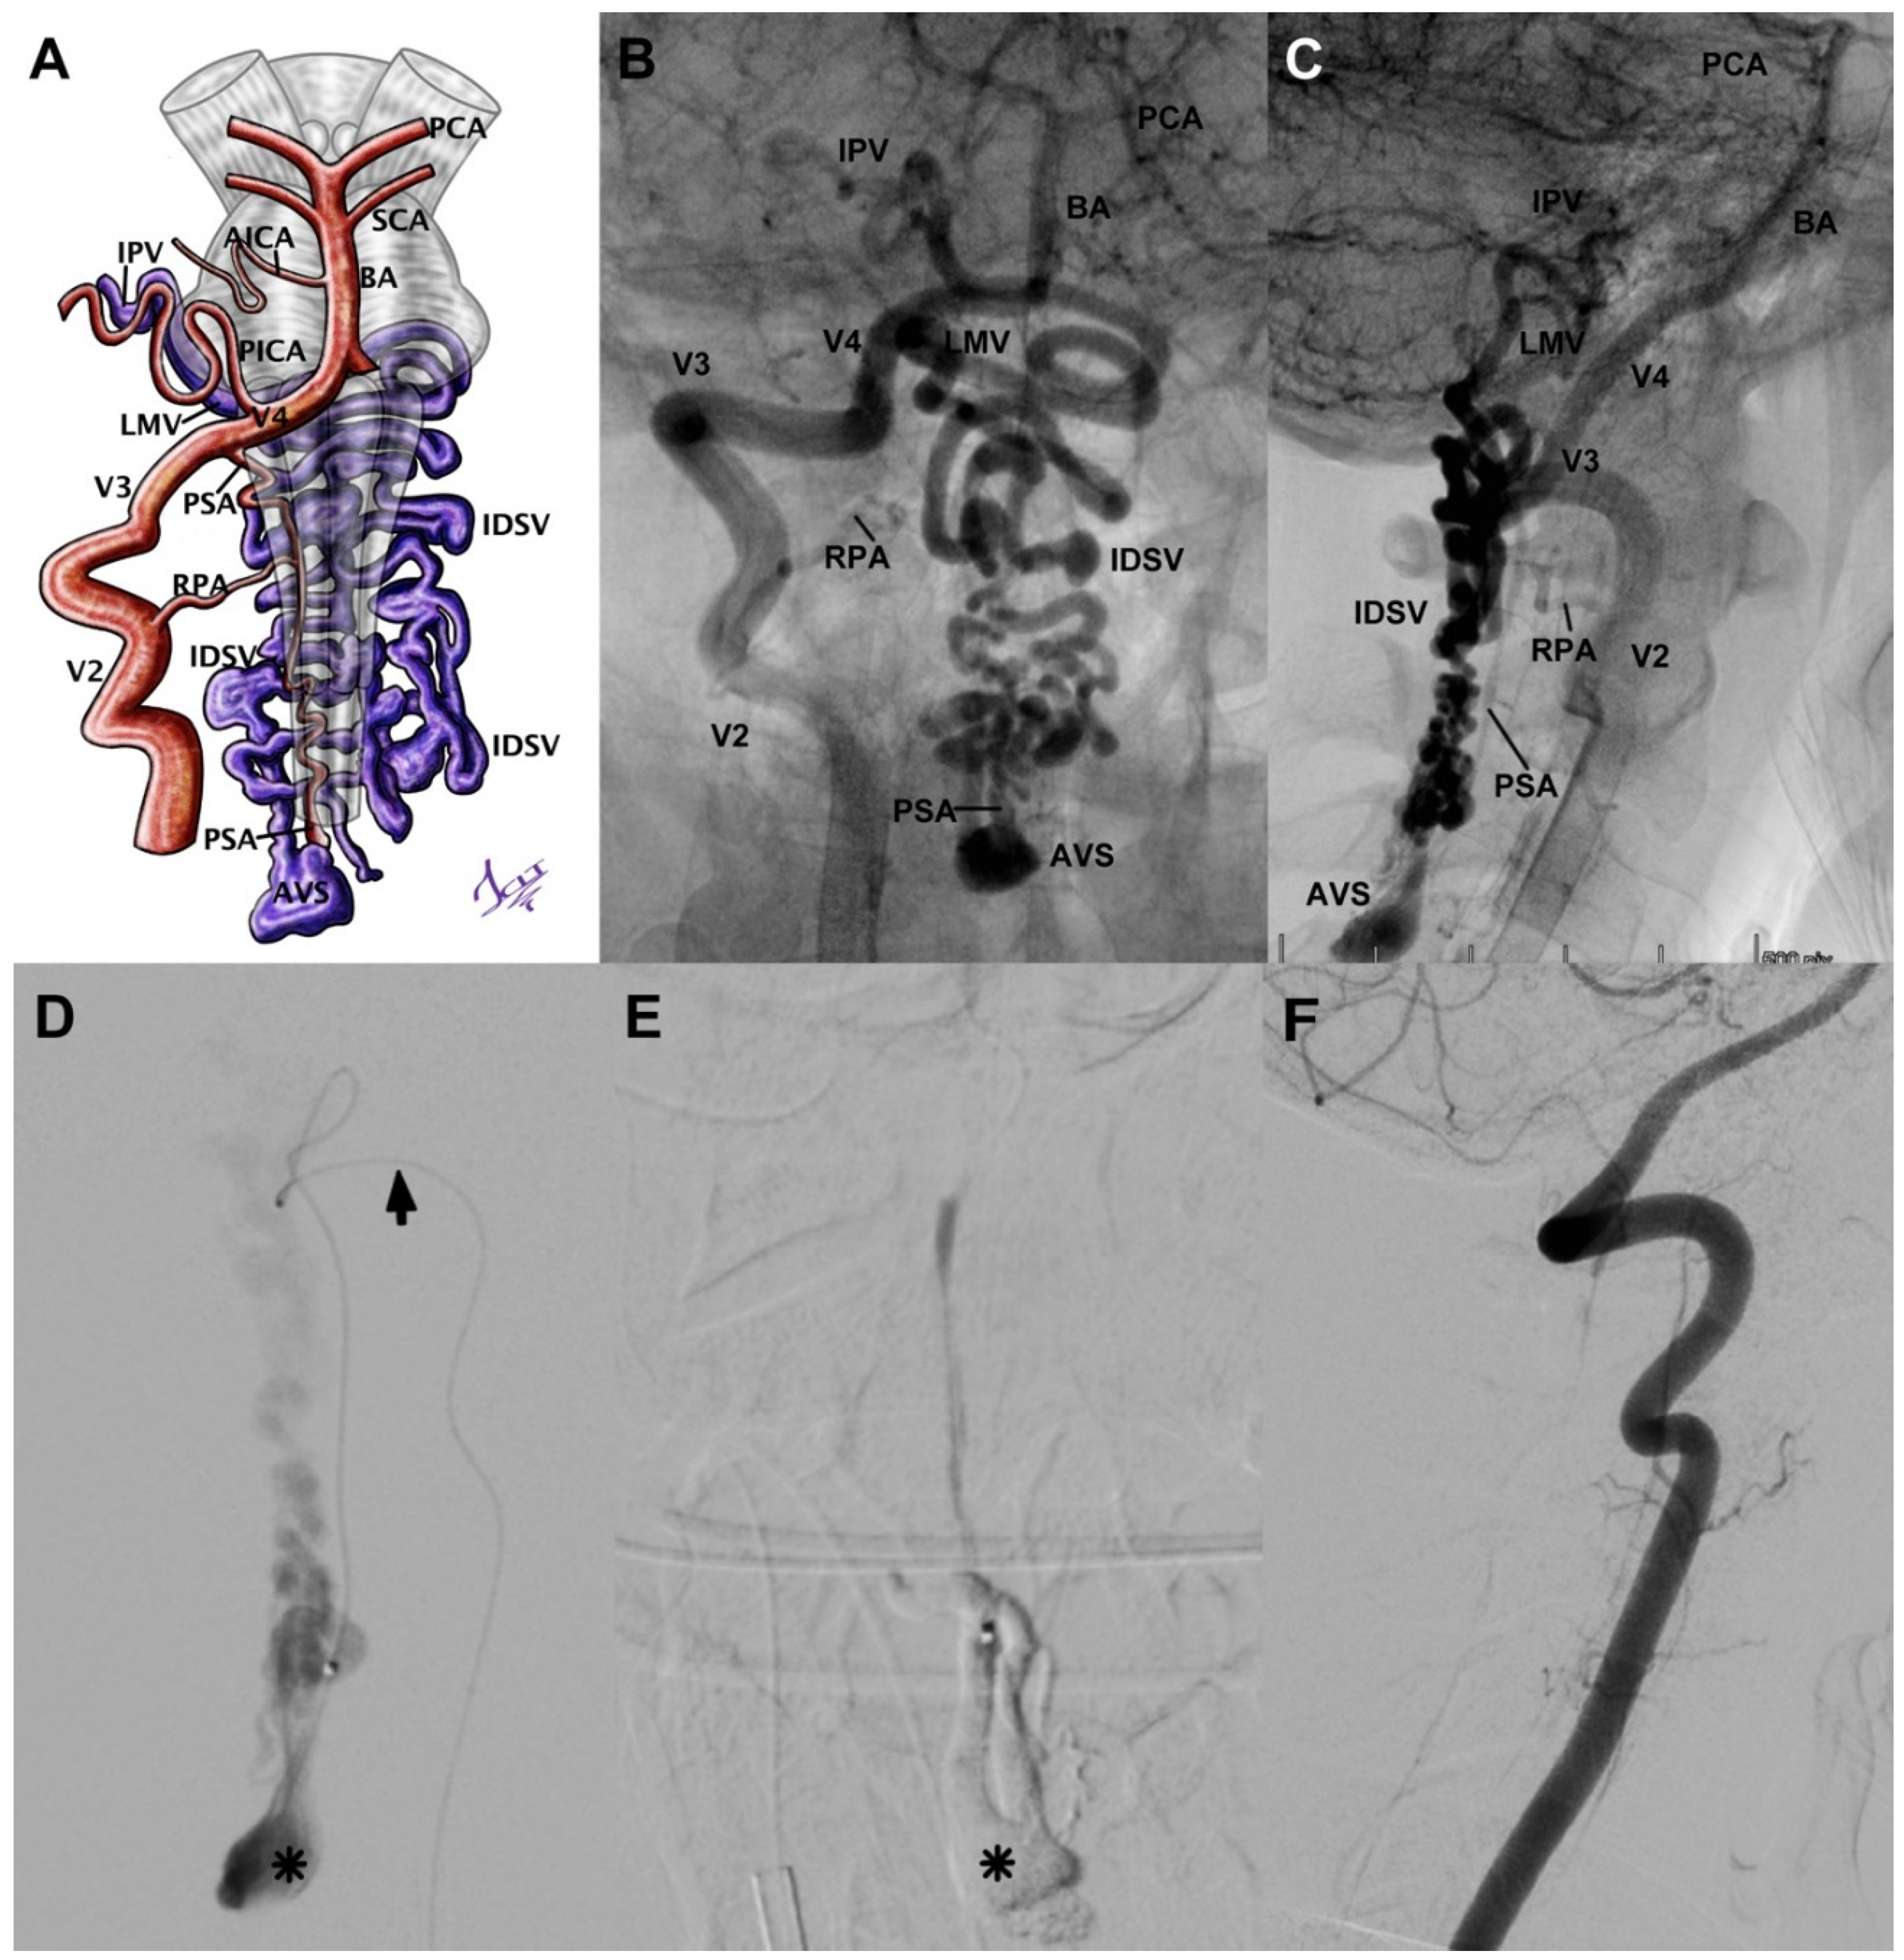

Case 7 was a 15-year-old female with SAH Fisher IV and negative angio-CT. An sDSA was performed, and it showed a CCJ AVF with afferent from PSA, the fistulous ostium also located at C2-C3, a venous aneurysm in contiguity, and the venous drainage toward the intradural varicose vein (Figure 2A–C). Subsequently, we proceeded to micro-catheterize the fistulous ostium and embolize it with Histoacryl (Figure 2D), achieving its total occlusion (Figure 2E,F). The patient was released without neurological sequel.

Figure 2.

(A) Schematic of an AFV case corresponding to the angiographies displayed in images (B) and (C). We consider a CCJ injury even though the ostium is at a C3 level, due to afferents and intracranial drainage. It shows (D) the catheterization through the posterior spinal artery (black arrow) and the venous aneurysm at the ostium level (asterisk). Histoacryl at the level of the fistulous ostium (E) and the aneurysmal dilation (asterisk). Angiographic control (F) shows complete absence of the lesion. BA = basilar artery, SCA = superior cerebellar artery, AICA = anteroinferior cerebellar artery, PICA = posteroinferior cerebellar artery, PCA = posterior cerebral artery, V2 = foraminal segment of vertebral artery, V3 = atlantic segment of vertebral artery, V4 = intradural segment of vertebral artery, PSA = posterior spinal artery, RPA = radiculopial artery, AVS = arteriovenous shunt, IDSV = intradural spinal vein, LMV = lateral medullary vein, IPV = inferior petrosal vein. Illustrated by J. Lizana.